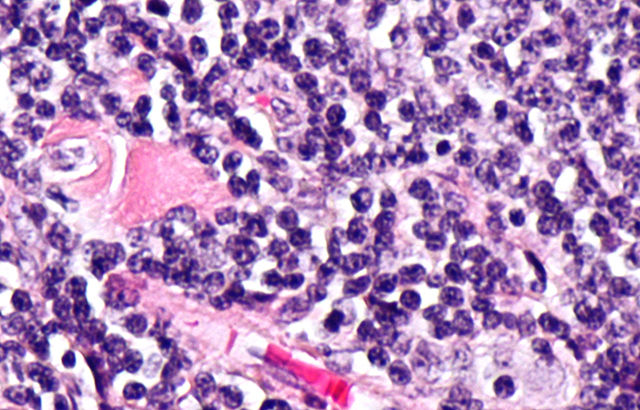

Micrograph showing follicular lymphoma

Follicular lymphoma is a common type of blood cancer and one of the most common non-Hodgkin lymphomas, with more than 2,500 people diagnosed in the UK every year. While the condition is normally responsive to existing therapies, the cancer often returns frequently and eventually develops resistance. For some, the cancer becomes more aggressive and difficult to treat.